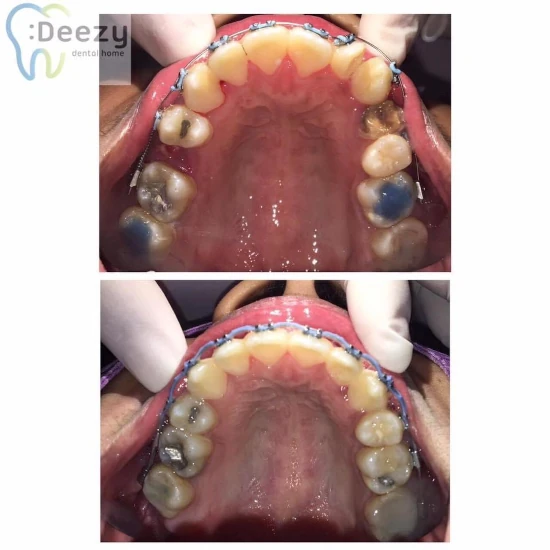

ลูกค้าจัดฟันทำฟัน

| จัดฟันแบบโลหะ | 36,000-45,000/เซต |

| จัดฟันแบบ aosc | 45,000-55,000/เซต |

| จัดฟันด้วยเครื่องมือ Damon/Clarity SL | 60,000-70,000/เซต |

| จัดฟันแบบใส Clear aligner | 500-8,000/เซต |